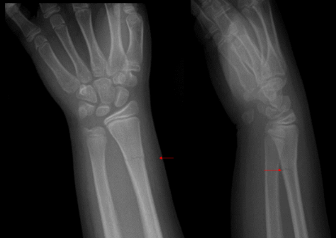

What findings are present?

Colle’s Fx